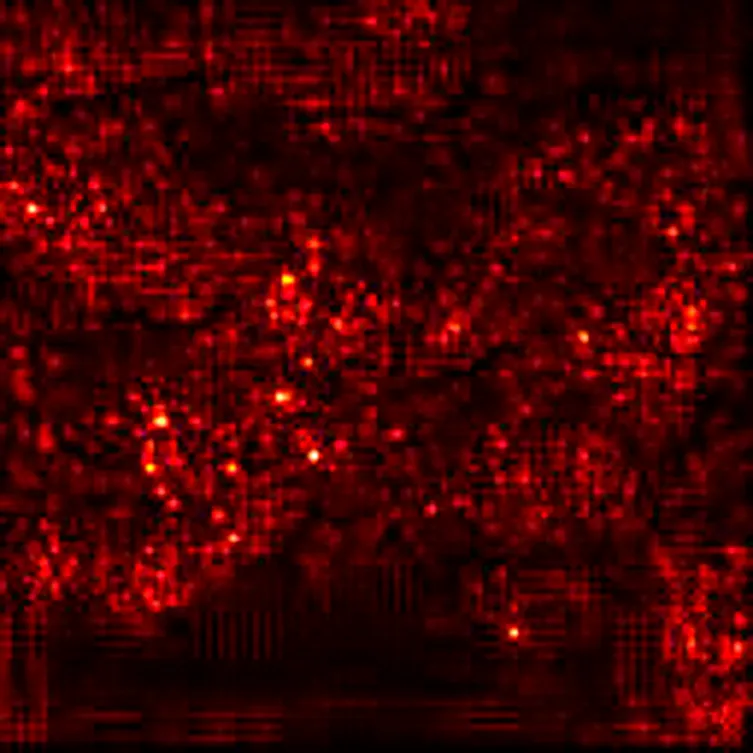

To further enhance interpretability, we selected one representative test image from each class—Normal, PCO, and Dominant Follicle—and analyzed the predicted class probabilities output by each model. Alongside each sample image, we also provide its corresponding Grad-CAM saliency map based on the best-performing model (ResNet18), which highlights the image regions that influenced the model’s decision. Table 7 presents these results, showing the image, its saliency visualization, and the predicted probabilities assigned by each model. This multimodal view helps illustrate how confidently and consistently each model responds to different ovarian conditions.

Table 7

www.frontiersin.org

Table 7. Predicted probabilities for representative images of each class across all models. Values are ordered as Normal, PCO, Dominant Follicle. Grad-CAM maps are from ResNet18.

To support model interpretability, we incorporated Grad-CAM visualizations using the best-performing architecture (ResNet18). These visual explanations highlight the specific regions of ultrasound images that influenced the model’s predictions, helping clinicians understand the basis of the classification. By providing visual cues linked to diagnostic decisions, such methods can improve trust in AI systems and facilitate their integration into clinical workflows. As shown in Table 7, combining probability outputs with saliency maps offers a more transparent view of model behavior across different ovarian conditions.